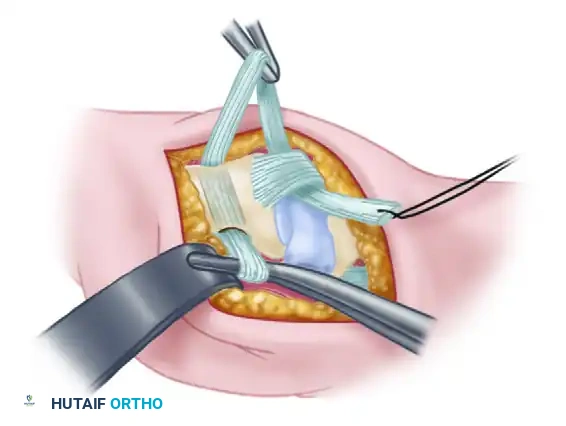

Figure: Path of the FCR strip rerouted to enter the volar channel at the beak of the metacarpal.

Intraoperative view showing the tendon strip being pulled dorsally through the metacarpal tunnel.